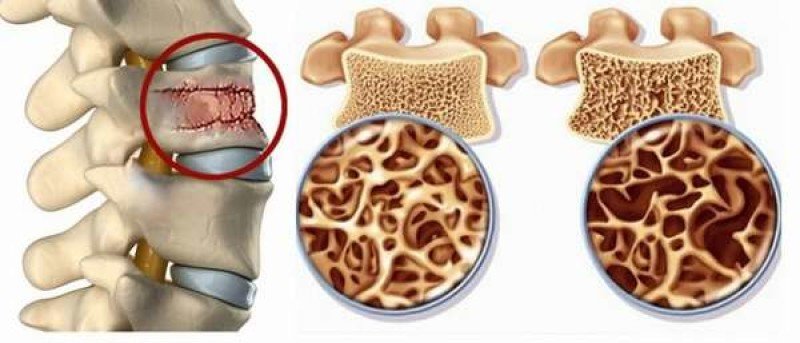

Рентгеновские снимки остеосклероза костной ткани